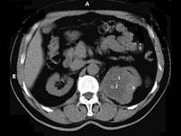

- 多项选择题男,65岁, 左侧腰背部胀痛伴无痛性全程血尿3月余,CT平扫及增强检查如图所示, 下列说法正确的是 ( )

A、平扫时见左肾上极有一软组织肿块影,其边界较清楚

B、增强扫描肾皮质期可见肿块明显强化,其内亦有无强化区

C、增强扫描肾实质期可见肿块强化迅速下降,但密度比平扫时仍要高

D、考虑为左侧肾癌

E、考虑为左侧肾错构瘤